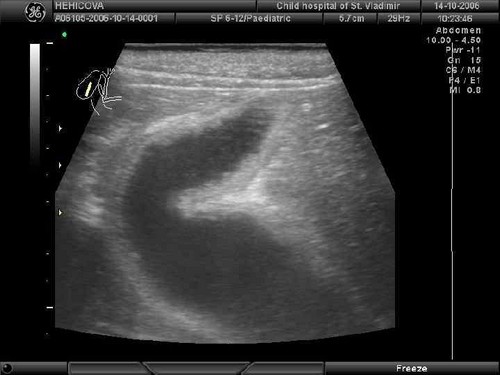

УЗИ является наиболее доступным и информативным методом для первичной диагностики. |

При образовании реактивных изменений симптомы чаще всего имеют скрытый характер, и точный диагноз устанавливается только после ультразвуковой диагностики.

Диагноз устанавливается при наличии нижеприведенных признаков во время ультразвукового исследования:

- Снижение плотности паренхимы и увеличение размеров поджелудочной железы свидетельствует о наличии острого панкреатита;

- Фиброзные изменения отличаются уменьшением размеров поджелудочной железы и увеличением плотности паренхимы;

- Развитие липоматоза обусловлено повышенным уровнем эхогенности и отсутствием изменения размеров органа. Во время УЗИ определяется наличие жировой ткани в паренхиме.

Скрининговым методом, определяющим наличие дополнительных образований, изменения в структуре и плотности органа, а также точные размеры железы, ее составных частей и главного протока, является УЗИ. Если этих данных оказывается недостаточно и диагноз неясен, назначаются дополнительные исследования.

Основным, самым удобным и безопасным диагностическим методом является ультразвуковое исследование, при котором, помимо ПЖ, изучают желчный пузырь и все паренхиматозные органы брюшной полости. При неповрежденной ПЖ эхографический метод показывает:

- нормальные размеры;

- однородную ткань;

- отсутствие диффузных или очаговых изменений.

Выявление изменений размеров и диффузных однородных нарушений в паренхиме, равномерно распределенных по всему объему органа, не является диагнозом, а характеризует состояние ПЖ на момент исследования. Играет роль плотность ткани — ее эхогенность.

При реактивном панкреатите имеется снижение плотности паренхимы, умеренные диффузные изменения и нормальные размеры ПЖ.

Значимое увеличение параметров и повышенная эхогенность характерны для острого панкреатита или выраженного обострения хронического воспаления. Увеличение плотности также наблюдается при липоматозных изменениях, когда нормальные клетки ткани замещаются жировыми.